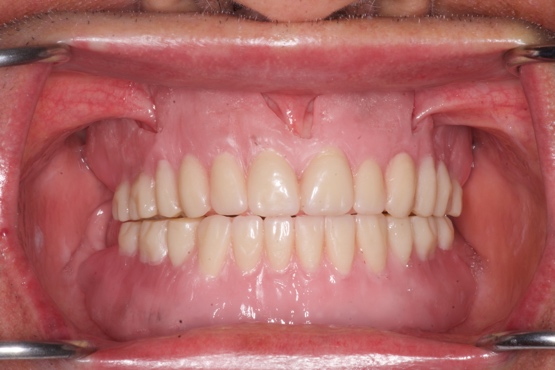

Se logró realizar la rehabilitación de un paciente edéntulo total mediante prótesis acrílicas utilizando la técnica de polimerización por medio de microondas.

Figura No. 2: Prótesis acrílicas colocadas en el paciente (A). Encajonado en el microondas (B).